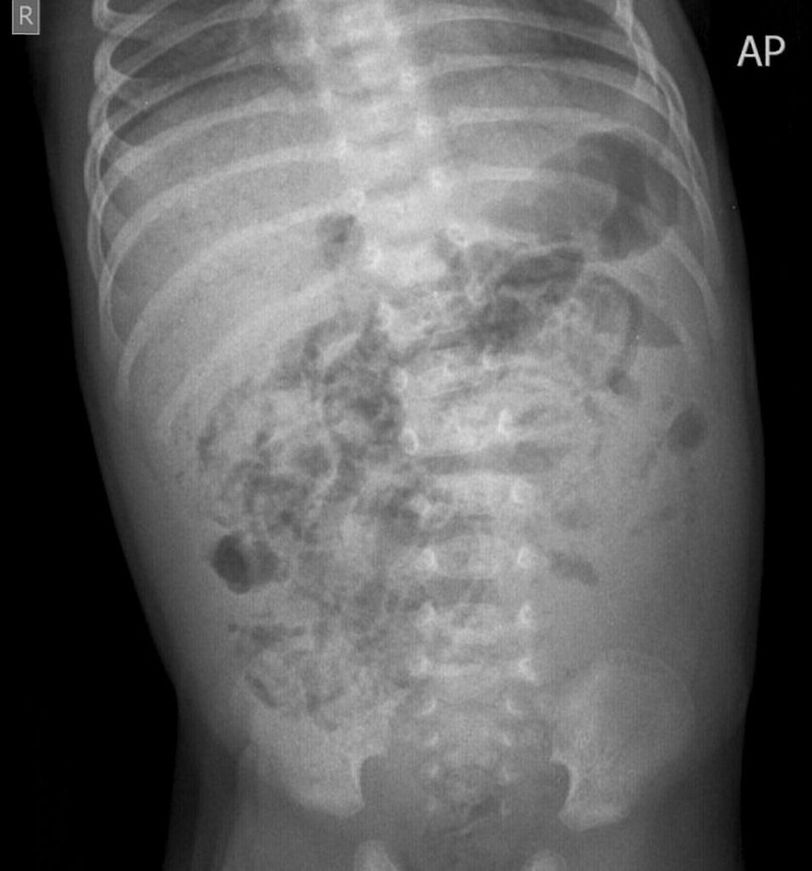

This abdominal X ray of a neonate shows pneumatosis intestinalis- gas in the gut wall. This condition can occur in a few diseases, one of them being Necrotizing Enterocolitis. Necrotizing Enterocolitis is a severe inflammation of the gut of the preterm baby. Several risk factors have been postulated and passage of microbes through the immature mucosa into the gut and blood likely plays a role. As the bacteria proliferate and intestinal wall undergoes necrosis, not only does the bowel lumen distend, but the gas also forms within the layers of the intestinal wall. From the intestine, the gas may also travel into the portal vein and give gas shadows in the liver. (Image via: www.radiopaedia.org)